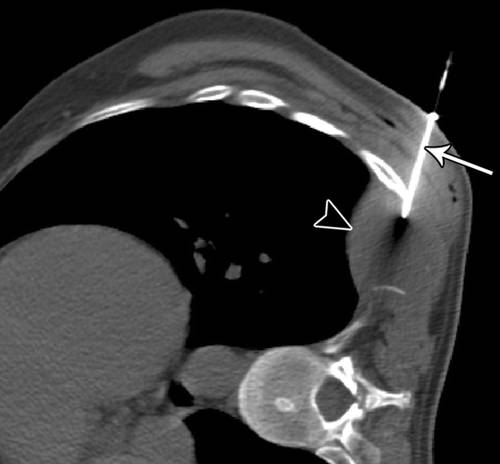

如果有相关的软组织肿块,肋骨活检的诊断结果更高(图15))。凸面表面,小体积和相邻的肺使这些活检具有挑战性。切线方法而不是一个垂直于胸膜有利于最小化气胸的风险。

![]()

15 - 35岁的女子转移性肾细胞癌。

胸部轴位CT扫描显示18号软组织活检针(箭头)采样胸壁肿块(箭头)